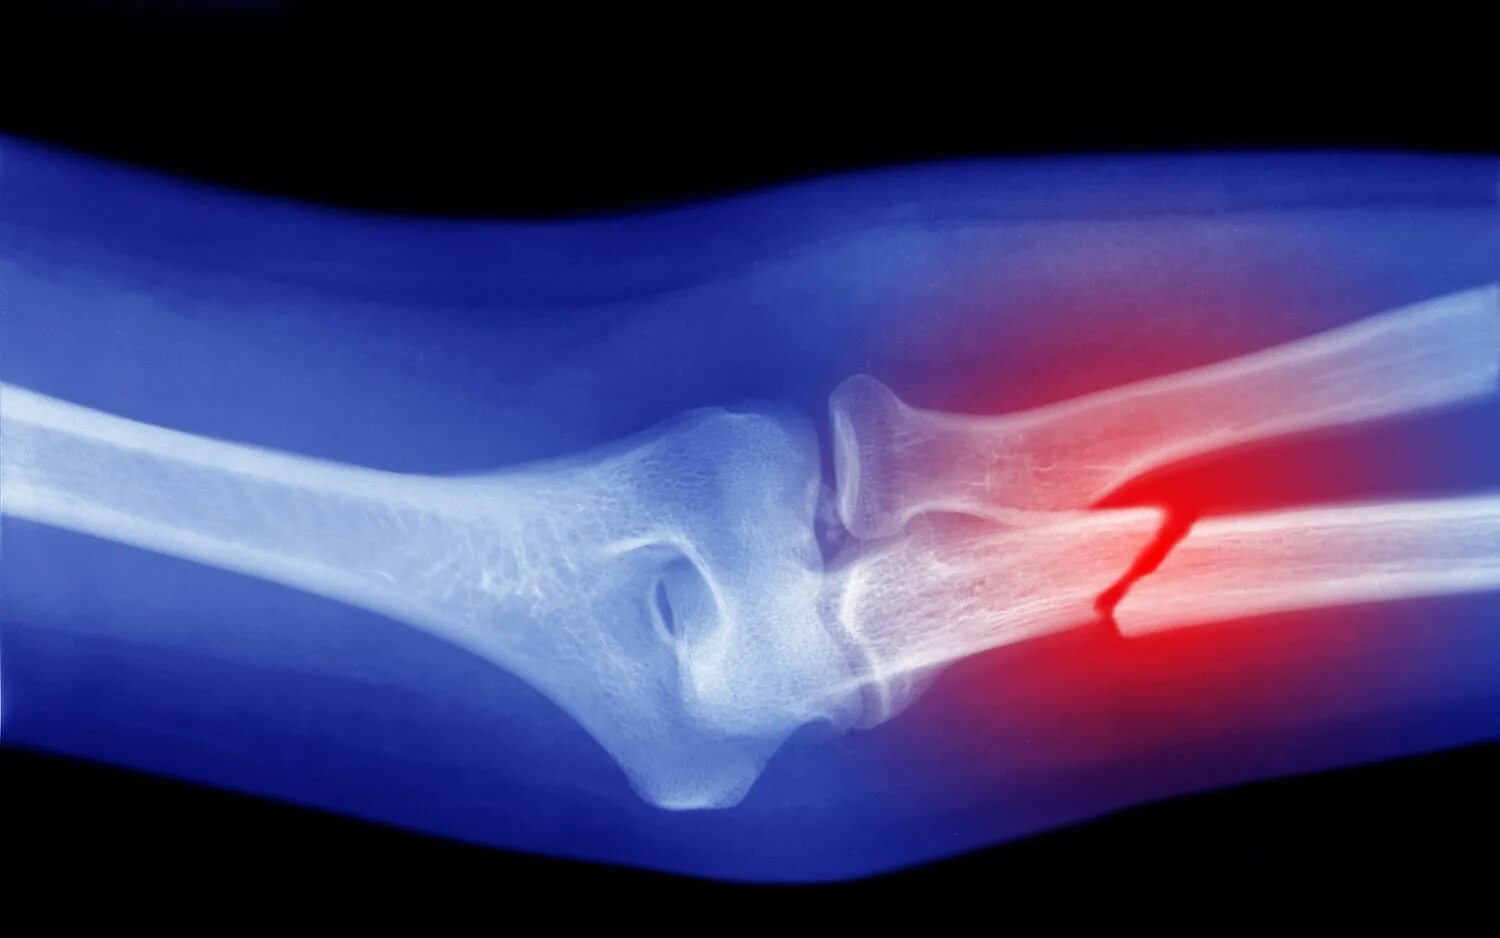

A fracture is a broken bone